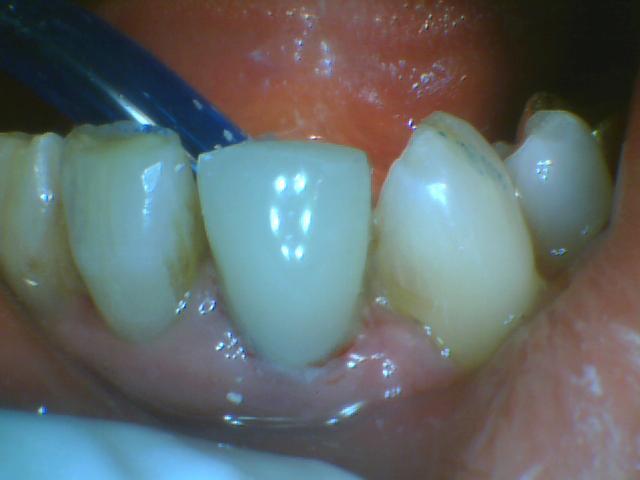

Είναι ο κεντρικός στην κάτω γνάθο(31). Αφού έγινε ενδοδοντική θεραπεία στην επόμενη συνεδρία τοποθετήθηκε προκατασκευασμένος ενδοριζικός άξονας. Αποκατάστάθηκε με ανασύσταση σύνθετης ρητίνης.